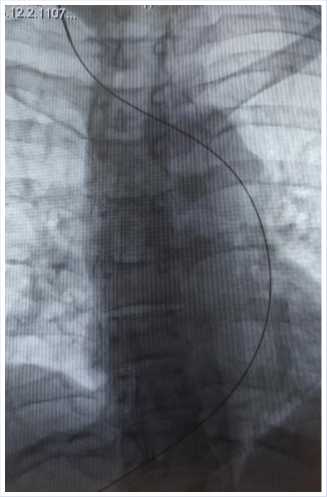

Решено было установить интродью-сер и провести катетер от порт–системы. Без технических сложностей был спозиционирован проксимальный кончик катетера на уровне пересечения с левым бронхом, проведен пробный забор крови (Рис. 2). Далее был сформирован подкожный «карман» для порт– системы в области дельтовидно-пекторальной бороздке справа, порт–система подсоединена к катетеру и имплантирована.

Рис. 2. Рентгенограмма установленной подкожной венозной порт-системы.